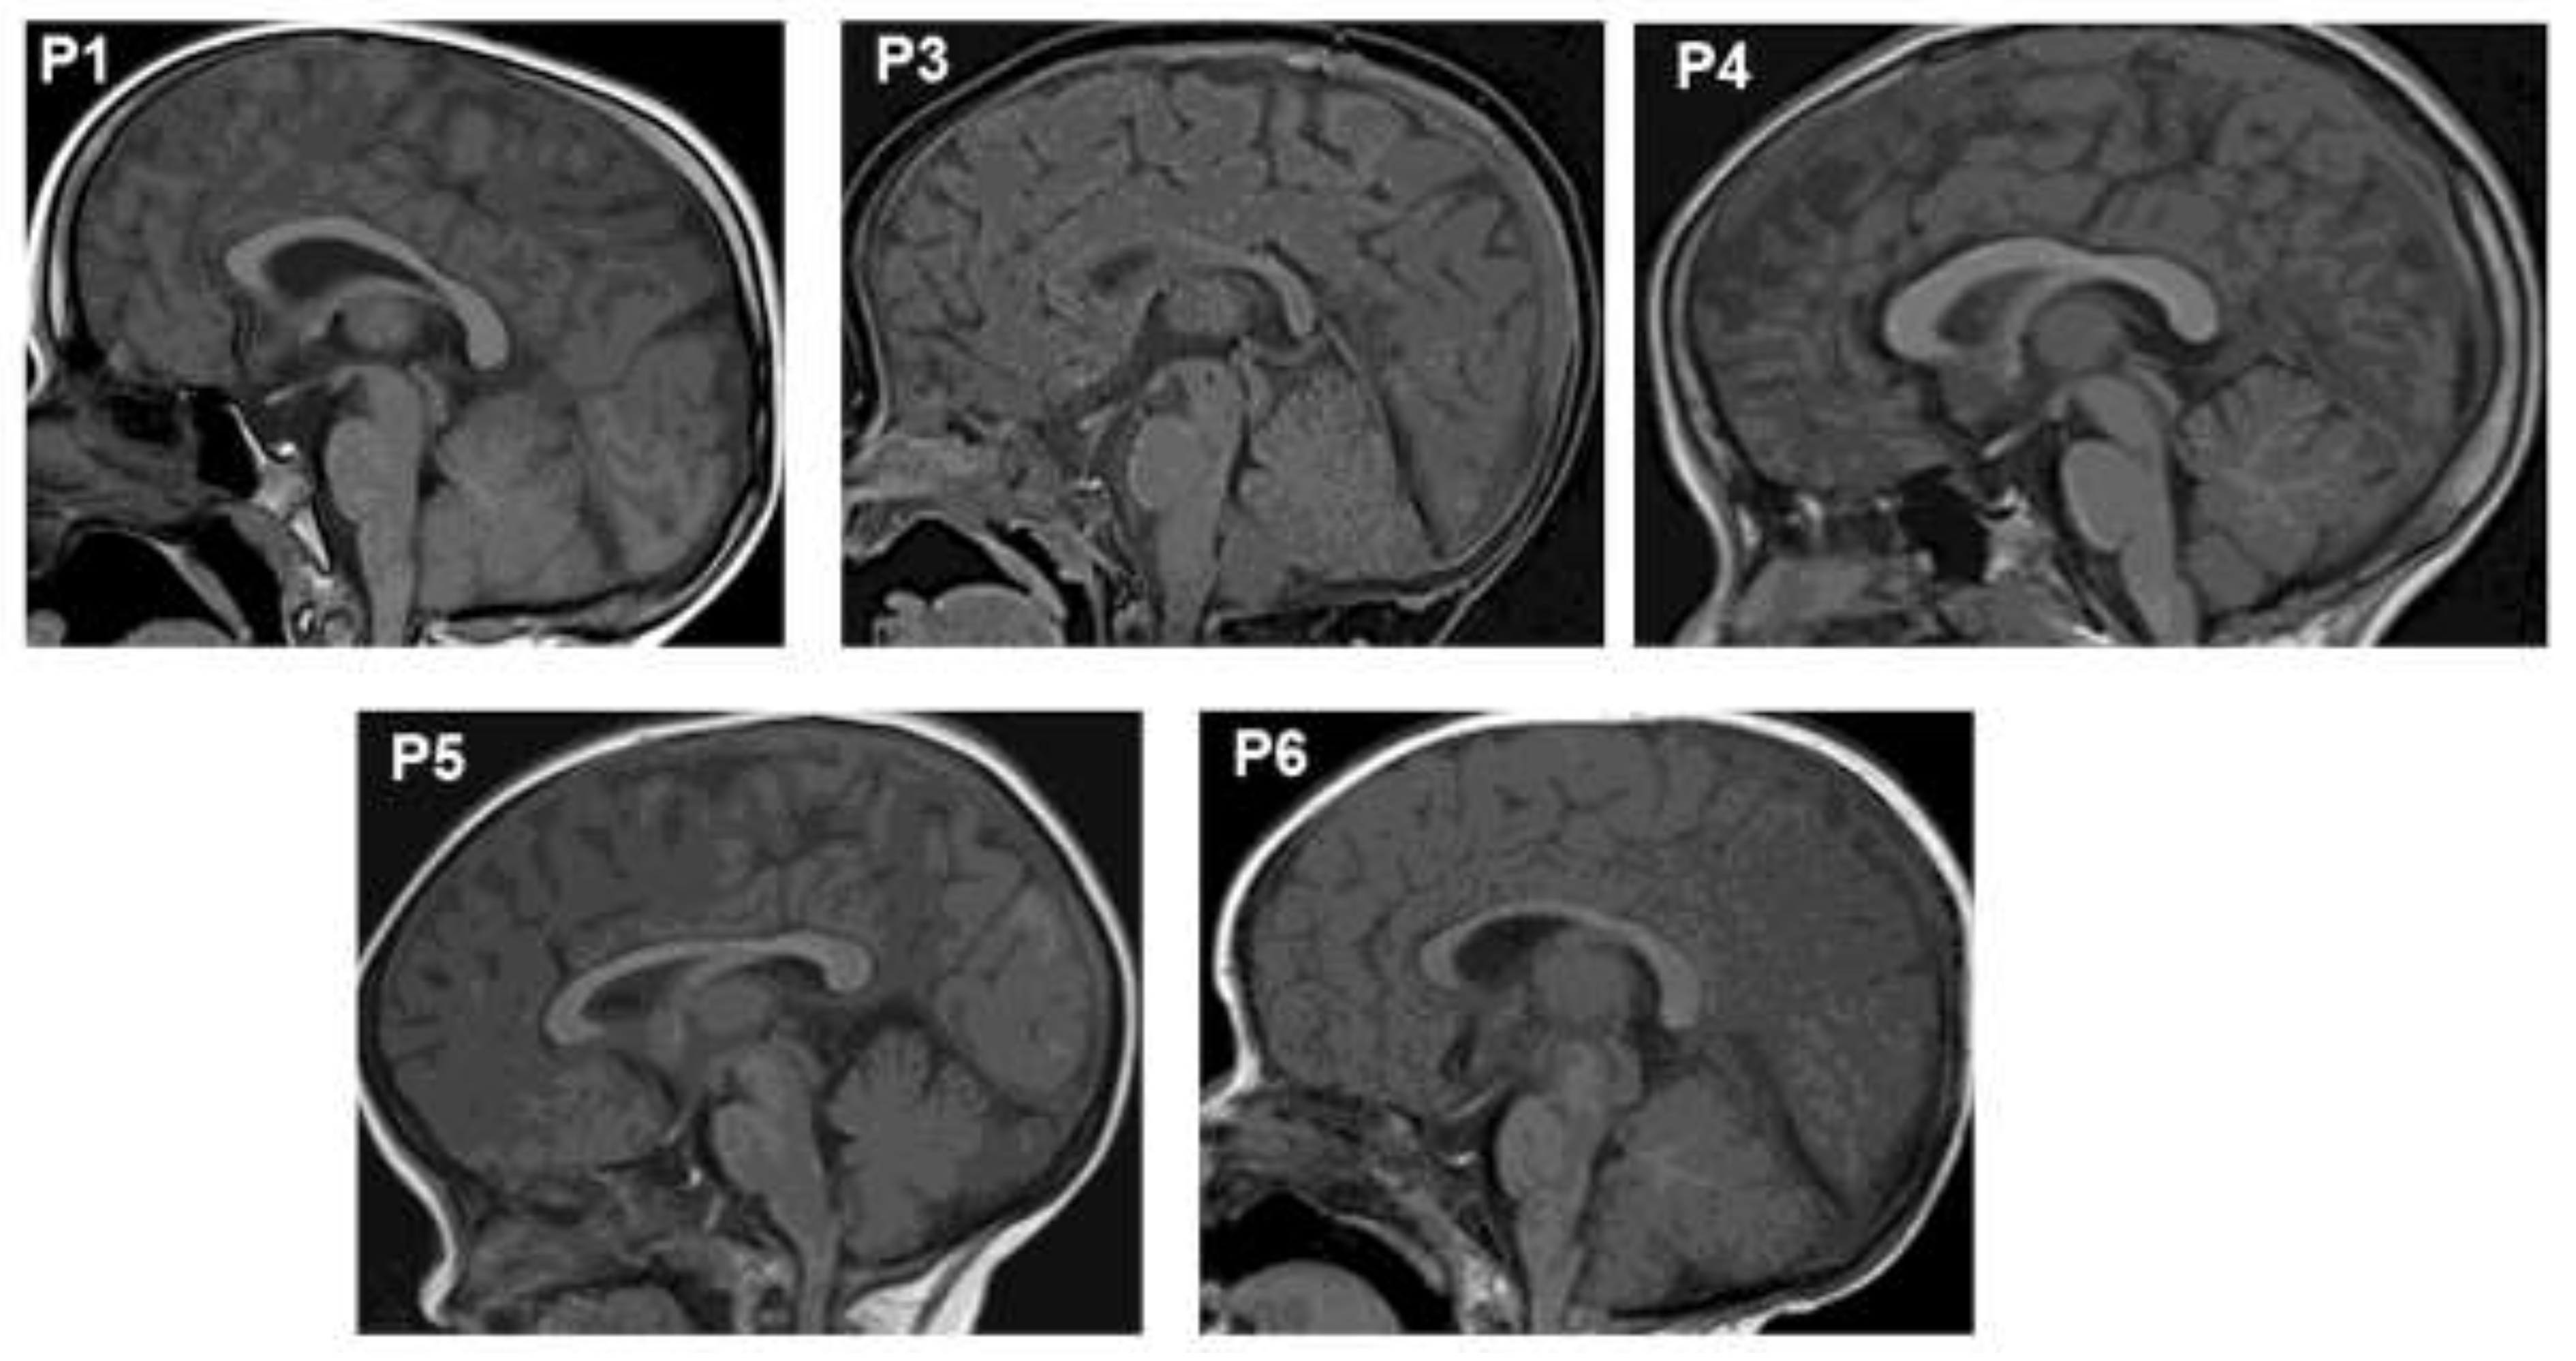

Brain magnetic resonance imaging (MRI) revealed anterior pituitary hypoplasia in all six patients (Figure 1). Patient P1 exhibited the most severely hypoplastic anterior pituitary, measuring 1.4 mm, compared to 1.6–1.7 mm in the other patients. The pituitary stalk and posterior pituitary gland were normal in all cases. All patients presented with thyroid hormone and growth hormone deficiencies (Table 1). At the time of diagnosis, P1, P2, and P3 had low levels of thyroid hormones (TSH and T4/FT4). Adrenal function was normal at diagnosis and remained so throughout follow-up. At diagnosis, IGF-1 levels were <15 ng/ml, and GH peaks were ≤0.3 ng/ml. Currently, patient P5 has completed puberty with normal levels of sexual hormones (LH: 4.02 IU/l). All patients exhibited prolactin (PRL) deficiency

In this study, we analyzed the phenotype, genotype, treatment, and outcomes of six Vietnamese patients with hypopituitarism. All six patients carried likely pathogenic or pathogenic variants in the POU1F1 gene. Brain MRI revealed anterior pituitary hypoplasia in all patients, a common feature in CPHD patients with POU1F1 variants [25]. No correlation was observed between pituitary size and patient age or variant type. The patients also exhibited physical characteristics such as midline hypoplasia, upturned nose, and protruding forehead [9,26].

Figure 1. Magnetic Resonance Imaging (MRI) revealed the anterior hypoplasia in the pituitaries of patients.